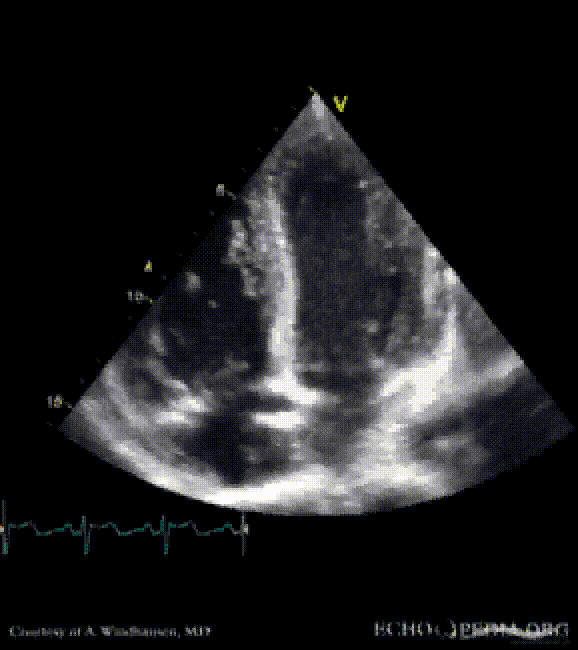

Severe Hypertrophic Cardiomyopathy (HCM)

Case description: Severe Hypertrophic Cardiomyopathy (HCM)

Courtesy of: A. Windhausen, AMC, The Netherlands

A2CH view A4CH view